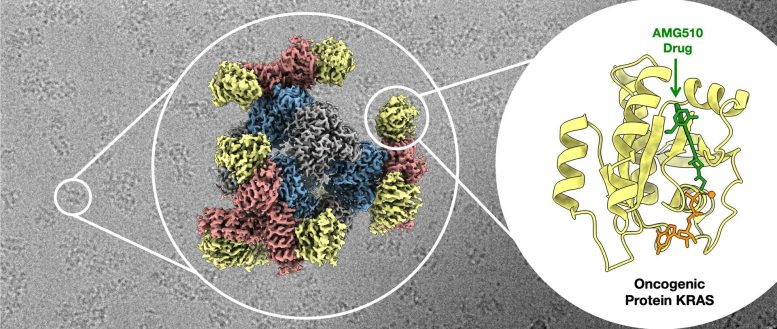

Une image au microscope électronique des échafaudages attachés à la protéine KRAS (arrière-plan). Le cercle de gauche met en évidence un échafaudage d’imagerie, le second affiche la structure 3D de l’échafaudage d’imagerie lié au KRAS et le troisième montre un gros plan du KRAS attaché au médicament anticancéreux AMG510. Crédit : Roger Castells-Graells/UCLA

Les chercheurs ont testé leur échafaudage en tentant de créer des images d’une protéine appelée KRAS qui encourage les cellules à proliférer. Il joue un rôle dans environ 25 % des cancers humains. Cela présente un intérêt particulier pour les chercheurs pharmaceutiques, car l’identification d’emplacements spécifiques sur la protéine liés à ses capacités cancérigènes pourrait aider les scientifiques à concevoir des médicaments neutralisant l’activité à ces emplacements, ce qui pourrait être une voie vers le traitement du cancer.

En utilisant le cryo-EM et l’échafaudage qu’ils ont développé, l’équipe dirigée par l’UCLA a pu observer la structure atomique du KRAS attaché à une molécule médicamenteuse étudiée dans le cadre d’un traitement potentiel contre le cancer du poumon. Leurs travaux ont prouvé que la nouvelle approche cryo-EM échafaudée peut éclairer la manière dont les molécules médicamenteuses se lient aux protéines cellulaires comme KRAS et les inhibent, et pourrait aider à orienter le développement de médicaments plus efficaces.

Selon Castells-Graells, les applications potentielles de cette nouvelle avancée ne s’arrêtent pas aux médicaments contre le cancer.

« Notre échafaudage est modulaire et peut être assemblé dans n’importe quelle configuration pour capturer et contenir toutes sortes de petites molécules protéiques », a-t-il déclaré.